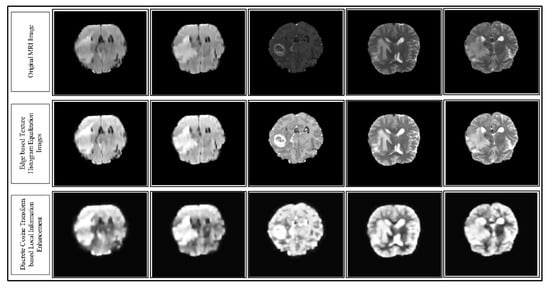

- We divided the image into two clusters based on a K-Means clustering algorithm and applied edge-based histogram equalization on each image. Further, the discrete cosine transform (DCT) was utilized for local information enhancement.

3.10. Results of the Contrast Enhancement